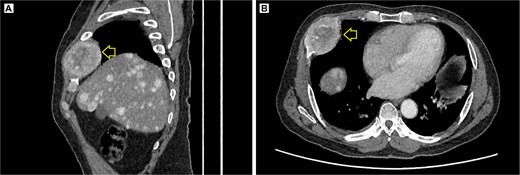

Contrast-enhanced pelvic CT scan. (A) Sagittal view of tumor in iliac crest. (B) Axial view of the iliac crest. Expansile soft tissue mass (arrow) of 113 × 96 × 100 mm, with central necrotic degeneration and heterogeneous contrast enhancement but predominantly peripheral.

Contrast-enhanced thoracic CT scan. (A) Sagittal view showing the tumor on the chest wall, involving a rib. (B) Axial view showing the tumor in the right costal arch. Expansile soft-tissue mass (arrow) measuring 45 × 38 mm in the right costal arch, with central necrotic degeneration and heterogeneous peripheral contrast enhancement.